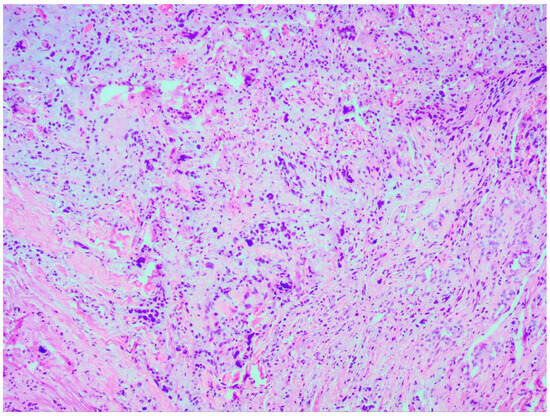

Thorough histopathological analyses highlighted the moderate formation of cellular material, consisting of spherical cells with pronounced nuclear polymorphism, multinucleated tumor cells, and an area of vascular proliferation (Figure 7). Multiple mitotic figures were visualized within the tissue. A histochemical analysis of the tumor tissue revealed the presence of positive glial fibrillary acidic protein (GFAP). Alpha thalassemia intellectual disability syndrome X-linked (ATRX) and isocitrate dehydrogenase 1 (IDH 1 R132H) were both negative. Antigen Kiel 67 protein (KI-67) was positive, but not elevated, around 20–25%.

Figure 7. Microscopic image of histopathological analysis, showing spherical cells with pronounced nuclear polymorphism, multinucleated tumor cells, and an area of vascular proliferation.